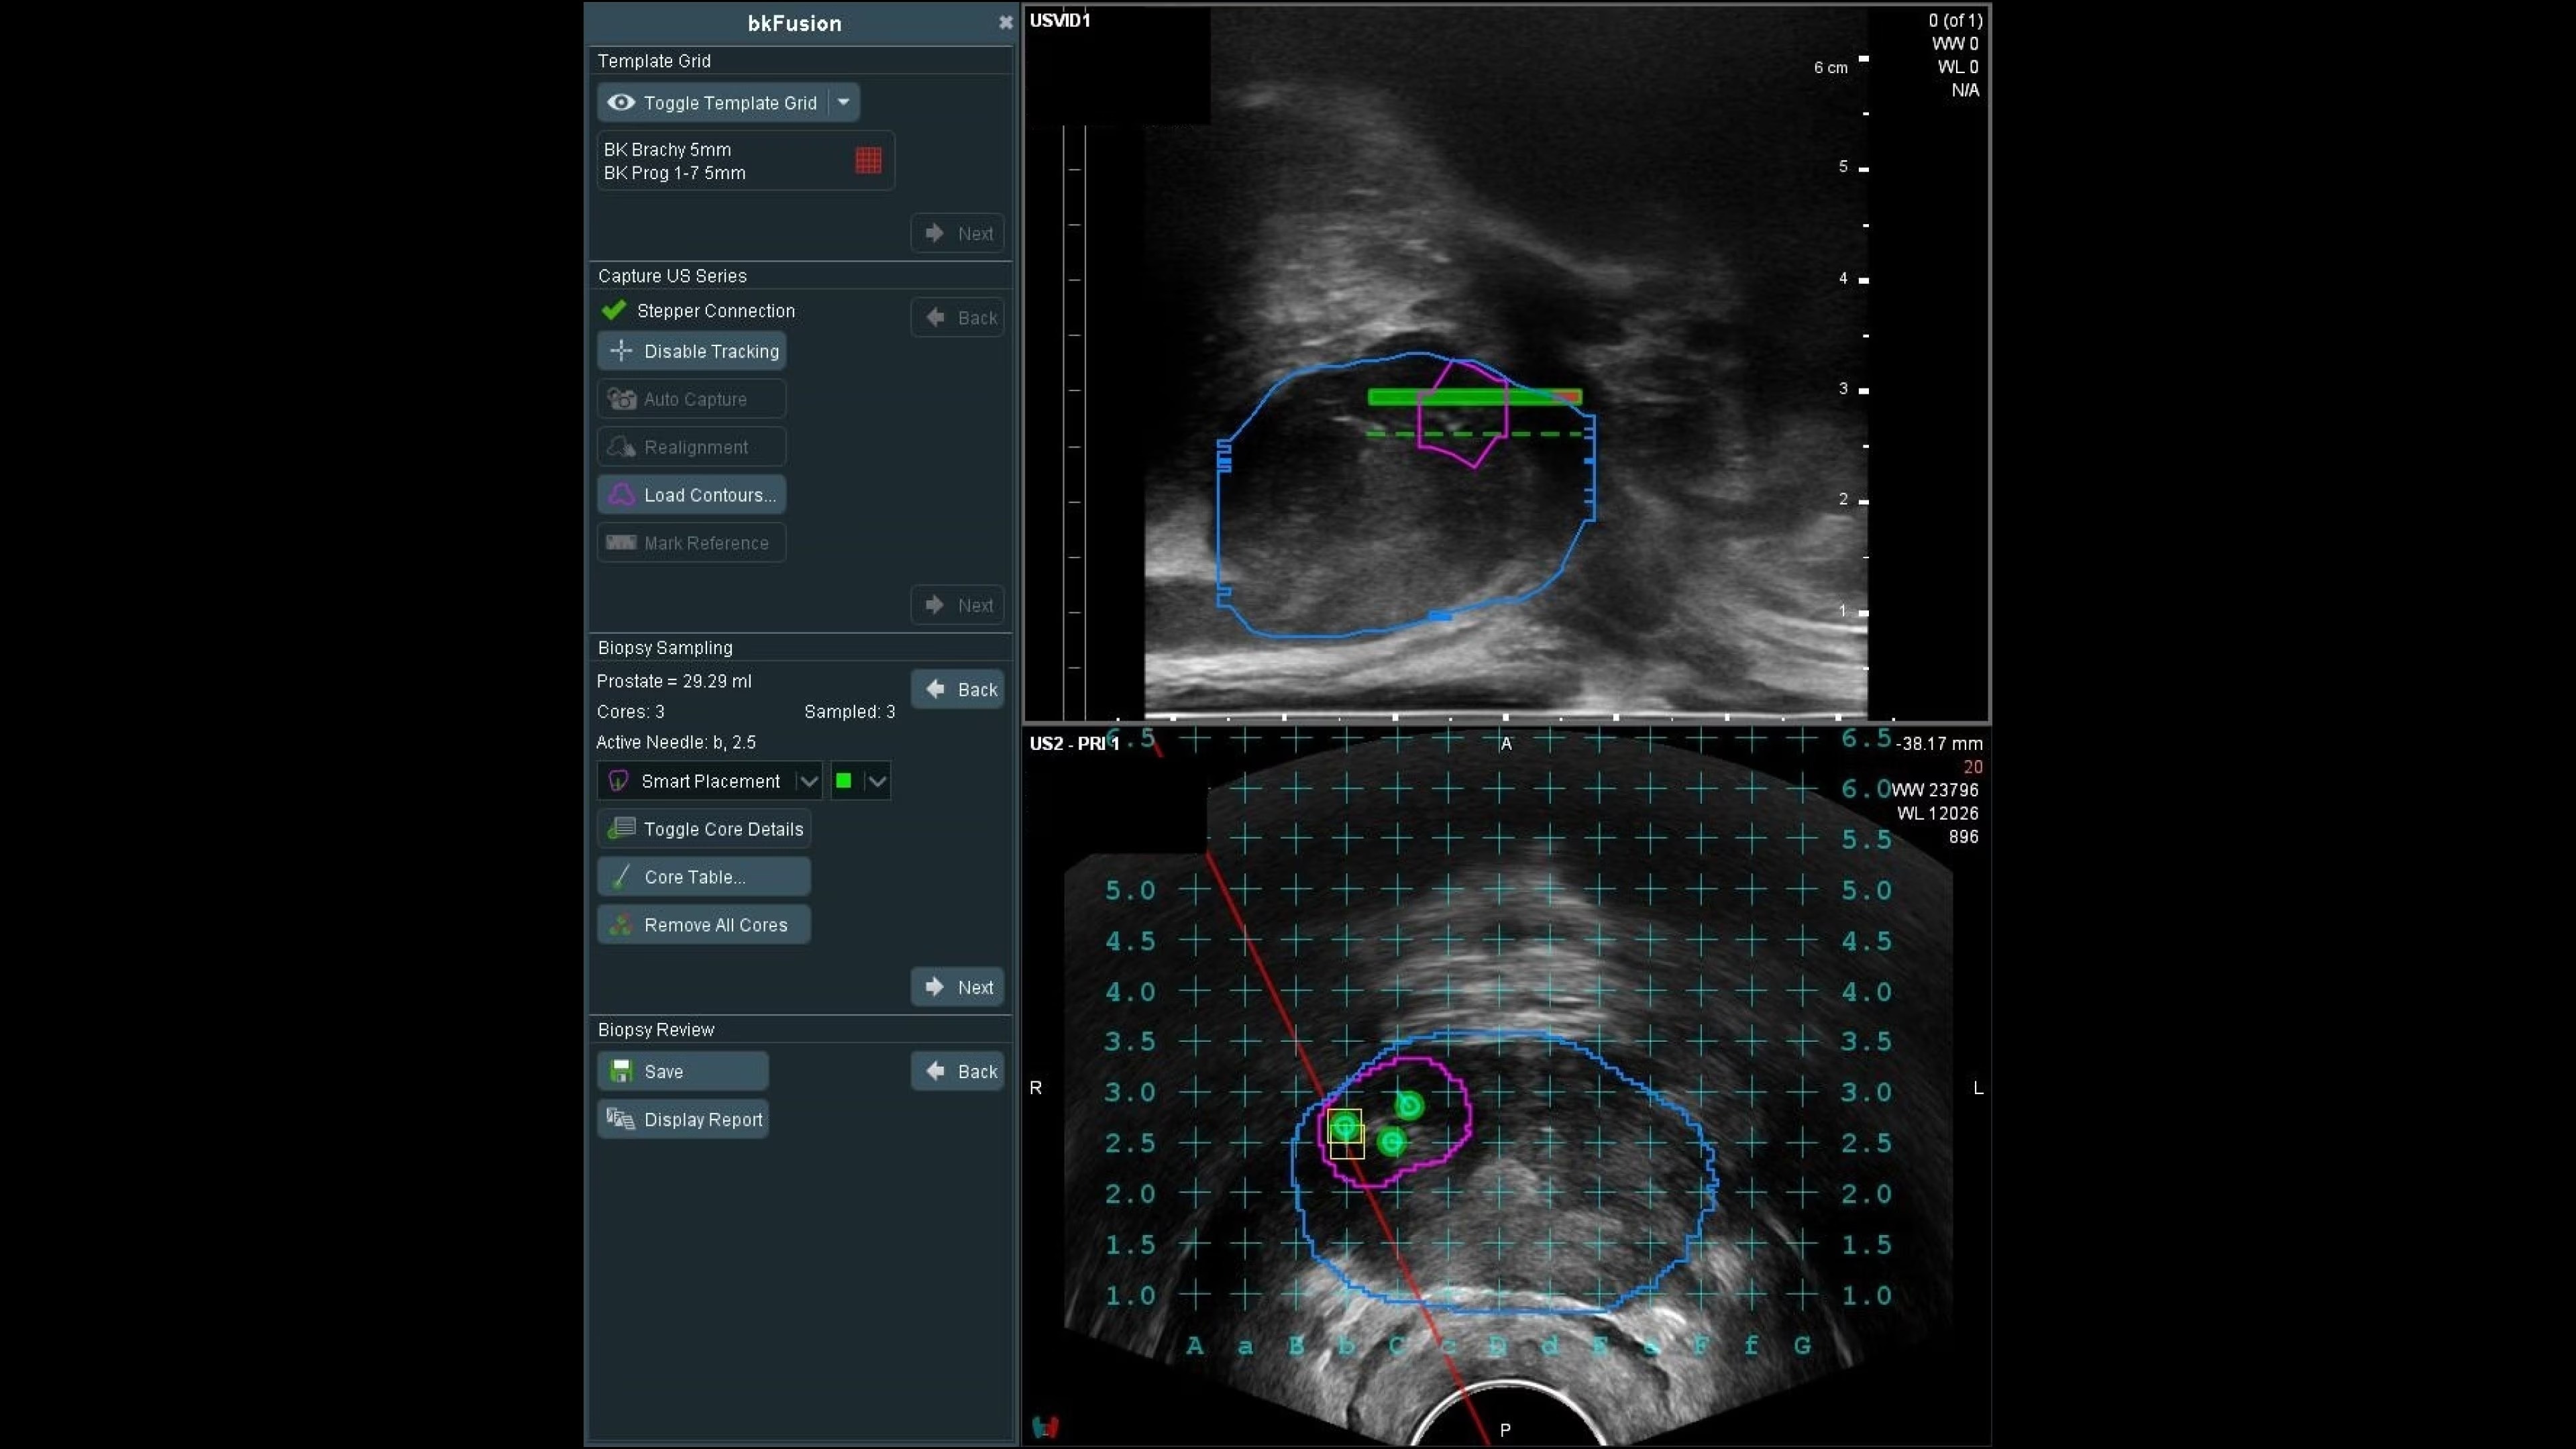

bkFusion–MRI-ultrasound Fusion Biopsy Solution

bkFusion offers advanced MRI-ultrasound fusion for high precision prostate biopsies. Benefit from high spatial resolution, fast workflow, and flexible biopsy options.

bkFusion is a fast, flexible, and effective MRI-ultrasound fusion prostate biopsy solution. Clinically proven to have effective detection rates¹, bkFusion offers a streamlined workflow designed for urologists. It provides the flexibility to choose from a range of options for transperineal and transrectal prostate biopsies. bkFusion is the only MRI-ultrasound fusion solution guaranteed to work with your ultrasound system, powered by unique Predictive Fusion® software for reliable image registration.

With bkFusion, confidently target your biopsy with clear visualization of organ borders to detect registration errors or deformations in real-time. bkFusion, MRI-ultrasound fusion biopsy solution features proprietary imaging algorithms developed with high spatial, temporal, and contrast resolution for advanced visualization.

bkFusion has proven to accurately detect 84% of PIRADS 3-5 lesions and up to 81% GG>=2 cancer.¹

Predictive Fusion® is the proprietary registration method allowing you to imediately see any errors in the overly of MRI and ultrasound images before and during the procedure. Utilizing rigid 2D slice registration, it eliminates distortion in merging 3D shapes, ensuring precise MRI-ultrasound fusion. If changes are needed, make simple, one-touch, micro-adjustments to updte the registration without calibration steps or 3D sweeps. Enhance your prostate biopsy accuracy with this advanced technology.